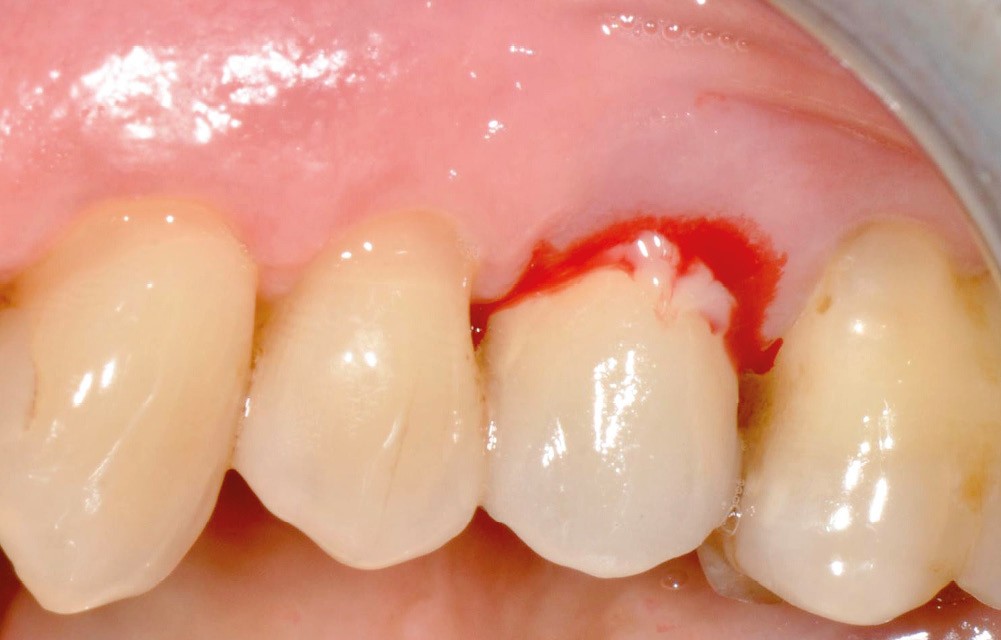

- Péri-implantite diagnostiquée en 2020